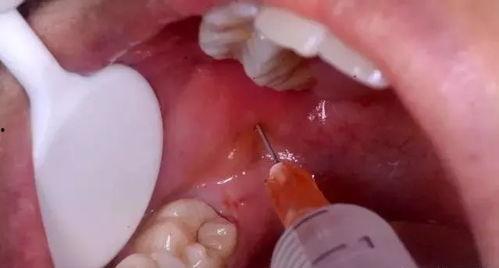

二、拔牙的步骤

下面,就让我带你一步步了解拔牙的具体步骤吧!

1. 定位牙齿:首先,要找到需要拔除的牙齿,并用手指轻轻触摸,感受牙齿的位置。

2. 固定牙齿:用拔牙钩轻轻插入牙齿的缝隙中,将牙齿固定住。

3. 旋转牙齿:用拔牙钳夹住牙齿,轻轻旋转,使牙齿松动。

4. 拔除牙齿:当牙齿松动到一定程度后,用力向上拔出牙齿。

5. 止血:拔牙后,用干净的纱布或棉球轻轻按压伤口,止血。